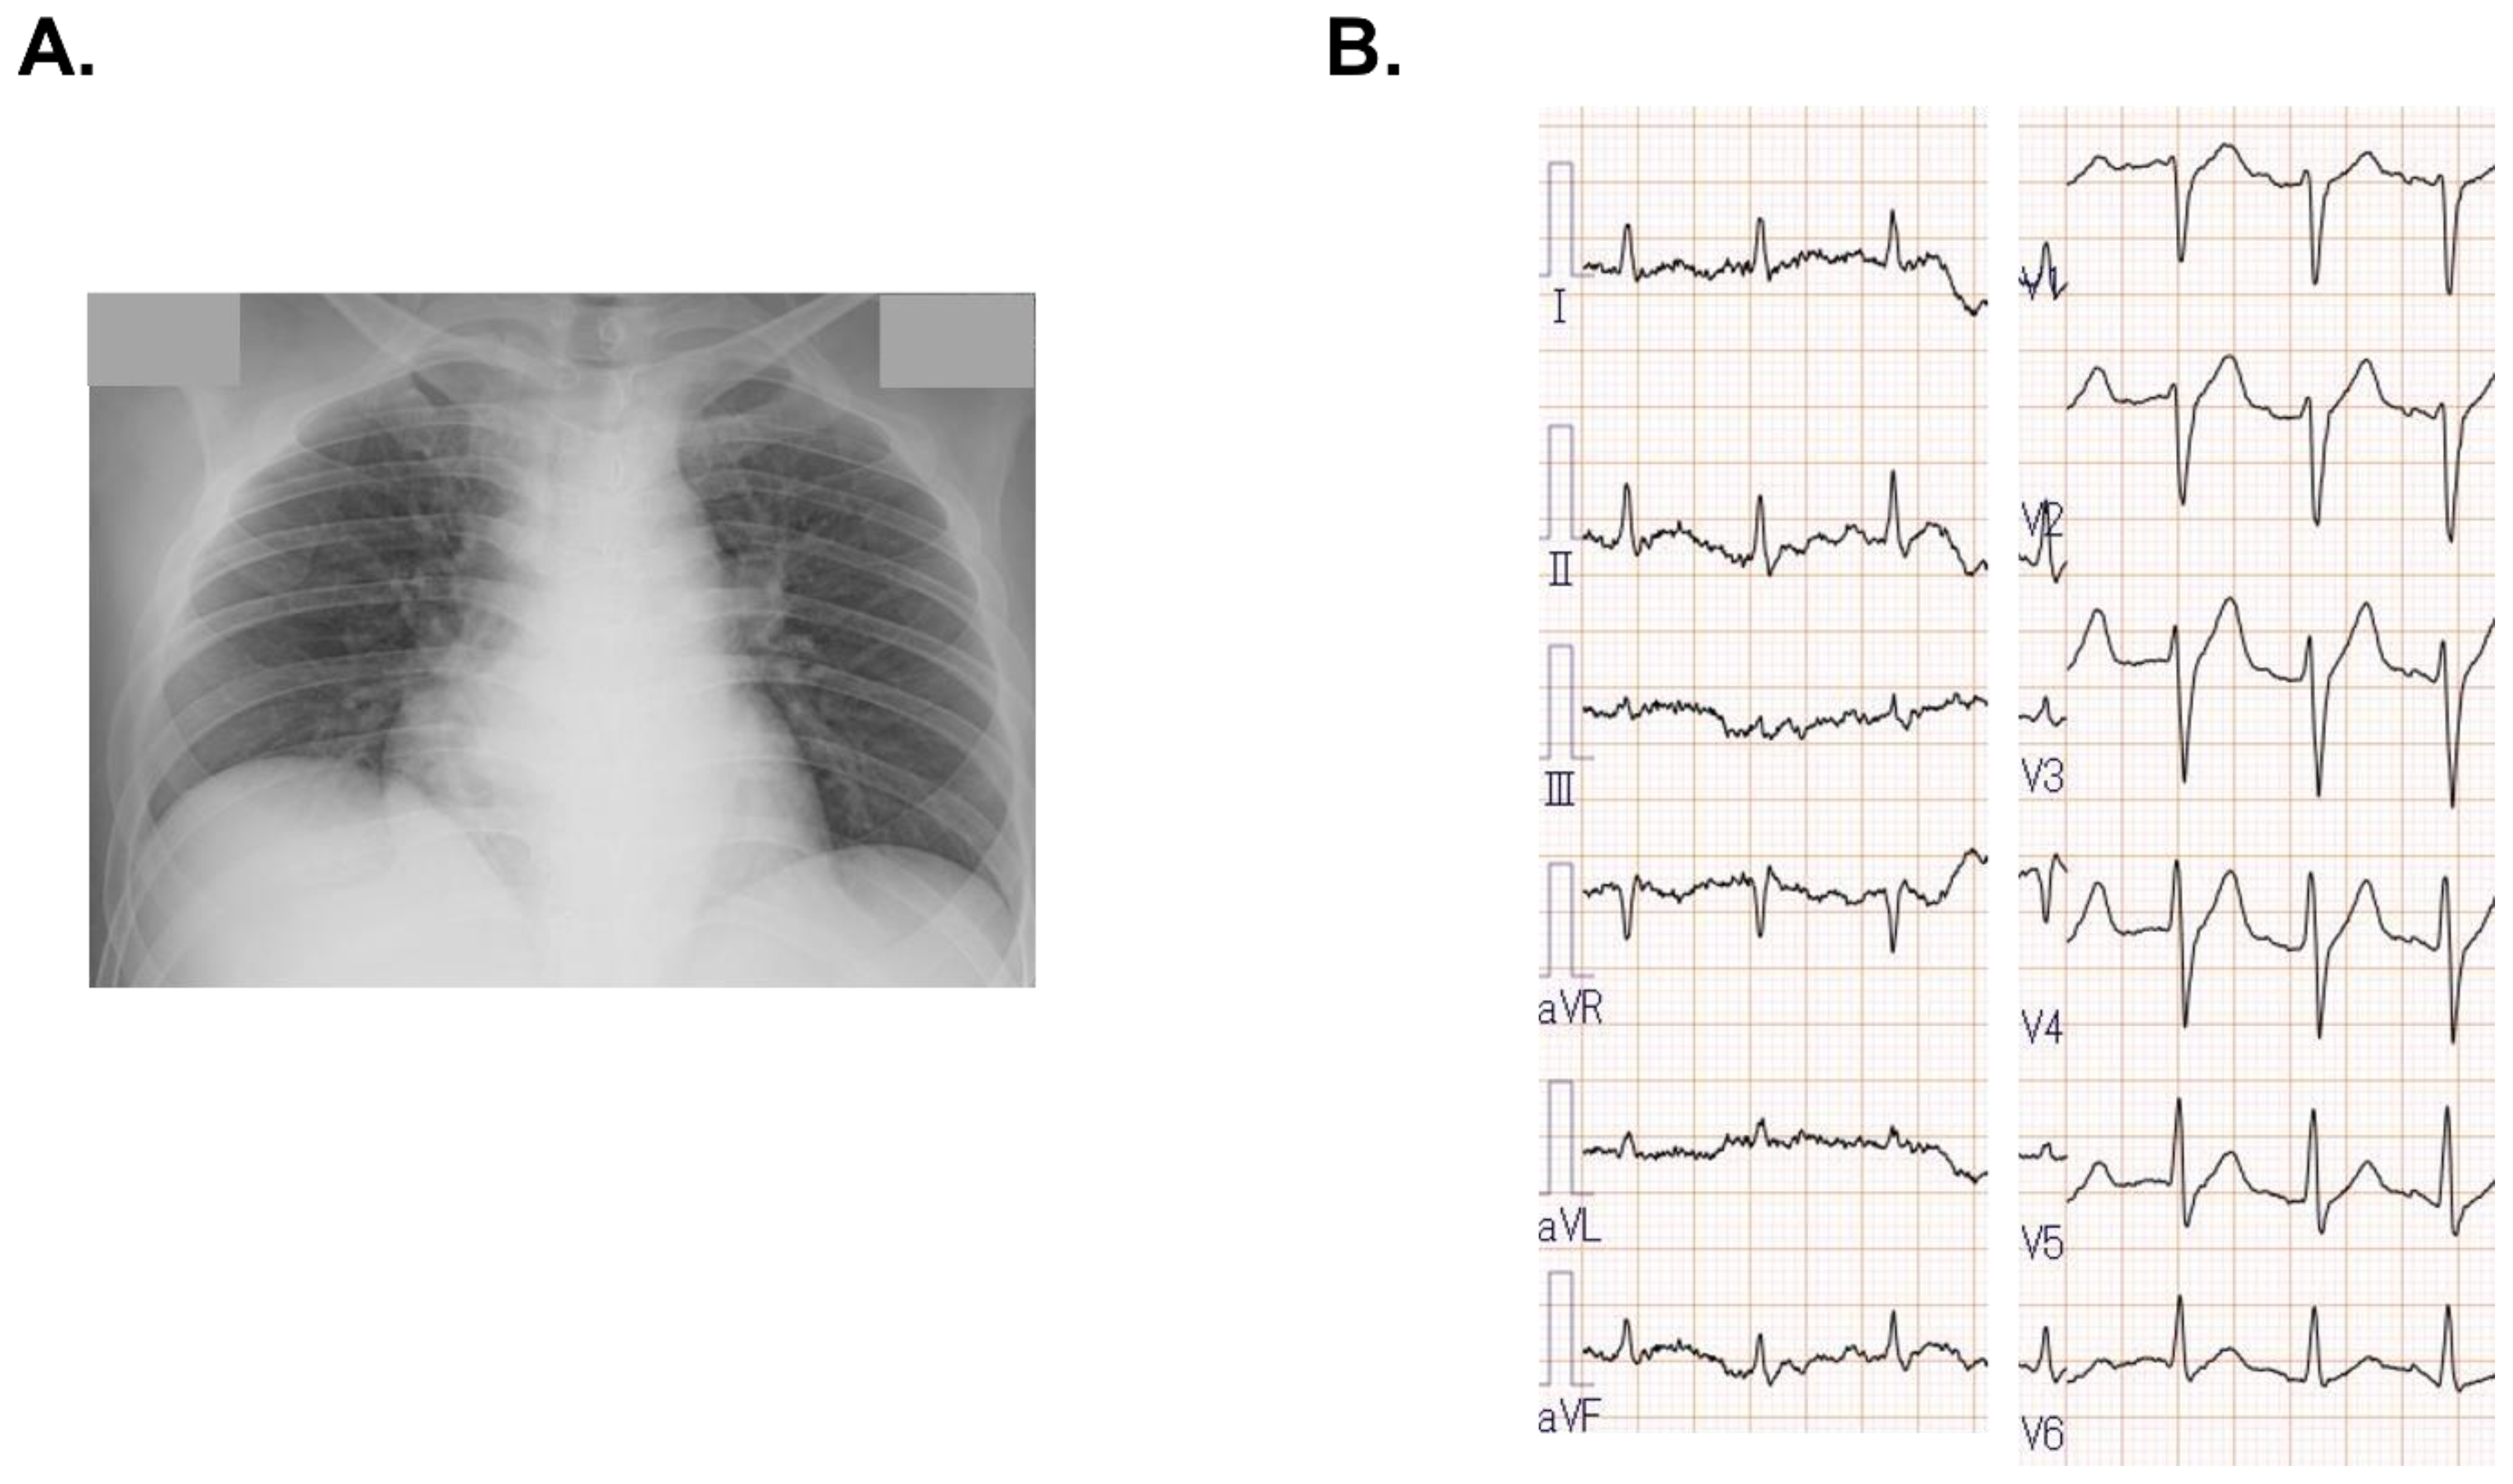

2.2. On Admission